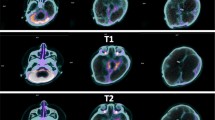

This patient was admitted at the age of 4 years at the Pediatric Intensive Care Unit (PICU) after a severe TBI secondary to a car accident. He underwent immediate resuscitation maneuvers and tracheal intubation. At admission in the PICU, the first neurologic examination showed a glasgow coma scale (GCS) of 4. Brain MRI showed deep and diffuse hemorrhagic petechiae, multiple frontal and temporal cortico-subcortical biemisferic hemorrhagic contusions, signs of axonal distraction at brainstem and at the splenium of the corpus callosum. Bilateral areas of increased T2 signal involving basal ganglia consistent with anoxic injury component were also detected (data not shown). After 7 days from the trauma the sedation was stopped and the child showed eye opening with a complete failure of respiratory trigger, so the patient underwent tracheostomy for mechanical ventilation and a placement of a gastrostomy tube. Six months after TBI the child showed a lack of swallowing, inability to speech, reflex movements without response to command and minimally conscious state in the presence of post-traumatic UWS. The neurological examination showed an alert and conscious child, severe communicative and neuropsychological impairment and complete dysphagia. The patient was fed only by gastrostomy. An oral-motor dyspraxia was also detected and only reflexed pattern movements were present. Increased muscle tone was observed, especially in the lower limbs with concomitant signs of spasticity. A targeted management of spasticity with botulinum toxin injection in specific muscle groups was performed without any improvement. The patient also received numerous physiotherapy cycles without any evidence of improvement in his communicative and cognitive skills and in his motor functions. Six years after TBI (at the age of 10 years), due to the persistent of post-traumatic UWS, treatment with intranasal hr-NGF administration was started, based on the schedule reported in Material and Method section. After NGF treatment, significant improvements were observed in some cognitive processes, mainly in the planning of a communication strategy, attention and verbal comprehension. At the end of intranasal NGF administration, the patient showed a substantial amelioration also in facial mimicry and in communicating by eyelids closure. The child was also able to eat from the mouth; in fact, some improvements were also observed in oral motility. The patient had a better relationship with his family members and all the caregivers and was less frustrated and in a better mood. Oral motor dyspraxia progressively improved too, with enhanced oral motility control including mouth opening, tongue motility, mastication and swallowing. The ability to feed also improved and the child became able to eat little amounts of food with a parent-reported better discrimination regarding taste. In association with the improvement in oral motor dyspraxia, other acquired skills, included phonation with more explicit emission of sounds, were observed. Some hand finger movements during play with characteristics of voluntary control have been observed and even improved muscular tone and tropism, with a significant amelioration of his spasticity. The child also reacquired the cough reflex and hiccups, previously absent. Based on the protocol, the child was subjected to PET, SPECT, EEG, and PSD before and after the treatment with hr-NGF. The first PET and SPECT pointed out a global reduction in tracer uptake at the cortical, subcortical and cerebellar levels (Figs. 1a and 2a, respectively). At the end of the treatment, both PET and SPECT showed an increase in tracer uptake in specific brain areas, such as in the bilateral temporal cortex, thalamus, left caudate nucleus and cerebellum. Figures 1b and 2b reported all detailed descriptions of neuroimaging modifications after the treatment. EEG recording performed before the beginning of hr-NGF treatment showed severe and diffuse low-voltage background activity. The EEG examination carried out after the end of NGF treatment showed an improvement in the electrical cerebral activity, mainly in the anterior regions with diffuse rhythms, while topographical analysis of the PSD distribution of the EEG signal documented a reduction in the slow frequency bands (delta and theta) in post treatment records, a more modest reduction in the alpha band, and an increase in the fast band activities (beta). These changes had a different distribution, as highlighted in Figures @@7a–e. These improvements of functional (PET/CT and SPECT/CT) and electrophysiological (EEG and PSD) findings, were confirmed by a concomitant amelioration of all the scales used to evaluate the neurological and clinical conditions of treated children. In particular, the mean GMFM pre-treatment was 2.78% (V level for GMCS for infant cerebral palsy). An improvement of GMFM of 22% was evidenced after the treatment, while also Ashworth scale showed an improvement in spasticity for ankles and lower limbs (from 3 to 2 scores). In addition, according to the DRS, this patient collected an initial score suggestive of a Vegetative State (22–24 points of the DRS). After the treatment with hr-NGF the child gained 4 points in this scale—thanks to a better communication strategy and motor response—going from Vegetative State to Severe Disability (17–21 points of the DRS). No adverse effects were reported during the study period.

PET before and after the treatment with hr-NGF. a, b: Brain 18F-FDG PET axial slices performed before (a) and after b intranasal hr-NGF treatment. A mild global reduction in 18F-FDG uptake was observed in all cortical regions, whereas a more marked reduction was detected in all subcortical regions (a). After hr-NGF administration, an increase in radiotracer uptake was found in the bilateral temporal cortex (right: + 7%; left: + 7%), right and left thalamus (+ 6% and + 4%, respectively) and the left caudate nucleus (+ 9%) (b)

SPECT before and after the treatment with hr-NGF. a, b: Perfusion SPECT images before (a) and after b intranasal hr-NGF administration. 99mTc-HMPAO SPECT images (transaxial slices) before hr-NGF treatment showed a mild reduction in radiotracer uptake (hypoperfusion) in the right and left parietal cortices, left frontal cortex, right temporal cortex, left temporal pole, as well as in the caudate nucleus, putamen and thalamus, bilaterally (a). After hr-NGF treatment, a slight increase in 99mTc-HMPAO uptake was detected in the left frontal cortex (+ 10%), right temporal cortex (+ 9%), left temporal pole (+ 13%), right and left caudate nucleus (+ 10% and + 11%, respectively), right and left putamen (+ 17% and + 15%, respectively), right and left thalamus (+ 11% and + 10%, respectively) (b)

A 17 old-month girl was admitted at our PICU after a severe crushing head injury by motor vehicle accident. At admission, the neurologic examination showed a glasgow coma scale (GCS) of 4. Brain MRI showed blood share in the lateral ventricles, deep and diffuse hemorrhagic petechiae, multiple frontal, temporal and occipital cortico-subcortical hemorrhagic contusions, signs of diffuse axonal injury at brainstem, at the splenium of the corpus callosum, involving nucleocapsular and midbrain regions (data not shown). After 6 days from admission, the sedation was stopped and the child showed a relative alert state. Due to the presence of respiratory failure, the patient underwent tracheostomy and a gastrostomy was placed to ensure appropriate nutrition. In addition, the patient developed central diabetes insipidus, panhypopituitarism, mild hyposurrenalism and impaired thermoregulation with tendency to hypothermia and bradycardia. At day 75 after TBI the child showed a lack of swallowing, inability to speech, reflex movements without response to command and minimally conscious state in the presence of post-traumatic UWS. The neurological examination showed an alert and conscious child with severe communicative and neuropsychological impairment and complete dysphagia. Increased muscle tone was observed, especially in the upper and lower limbs, with initial signs of spasticity, not responding to botulinum toxin injection. Thirty-one months after TBI (at the age of 4 years), due to the persistent of post-traumatic UWS, treatment with intranasal hr-NGF administration was started. At the end of intranasal NGF administration, the patient showed a significant improvement in facial mimicry. The child was also able to eat from the mouth; in fact, some improvements were also observed in oral motility and head rotation. Oral motor dyspraxia progressively improved too, with enhanced oral motility control. In association with the improvement in oral motor dyspraxia, other acquired skills, included phonation were observed. Moreover, during the cycles of hr-NGF therapy, a progressive but constant enhancement of head movements (mainly in head lateral rotation and minimally in up and down movements) was reported. Some hand finger movements have been observed with improved muscular tone, tropism, and spasticity. A recovery of some hypothalamic functions, such as an improvement in thermoregulation, cardiac rhythm, and in the sleep–wake cycle, were also detected. The child underwent PET, SPECT, EEG, and PSD before and after the treatment with hr-NGF. The first PET and SPECT pointed out a marked and severe reduction in tracer uptake at the cortical, subcortical and cerebellar levels (Figs. 3a and 4a). At the end of the treatment, both PET and SPECT showed a remarkable increase in tracer uptake in specific brain areas, such as bilateral temporal, parietal, and occipital cortex, thalami and cerebellum. Figures 3b and 4b reported these modifications after the treatment with hr-NGF. EEG recording performed before the beginning of hr-NGF treatment showed severe low-voltage background activity, with sporadic theta-delta activity in the right and left fronto-temporal and occipital regions. The activity was markedly and diffusely depressed with a poor electric organization. The EEG examination carried out at the end of NGF treatment showed an improvement in the electrical cerebral activity: a quantifiable 4–5 Hz background theta-delta activity is evident bilaterally on the anterior and posterior regions, intermixed with abundant diffuse rapid rhythms. Topographical analysis of the PSD distribution of the EEG signal documented a reduction in the PSD of the slow frequency bands (delta and theta) in post treatment records, a more modest reduction in the PSD of the alpha band, and an increase in the fast band activities (beta). These changes had a different distribution, as highlighted in Figures @@7a–e. All these clinical and neuroradiological findings were confirmed by the GMFM scale that increased from 3 to 6.8% and by the Ashworth scale that highlighted an improvement in spasticity for the right side of the lower and upper limbs (3 points). Regarding the assessment of the degree of disability, the total DRS was 24 before the treatment, indicative of a vegetative state. The areas of greatest impairment were autonomy, ability to perform personal activities and employability. After the treatment, a 3-point improvement on this scale was observed with the switch from a vegetative state to a severe disability (21 points of the DRS). No side effects were reported during the study period.

PET before and after the treatment with hr-NGF. a, b: Brain 18F-FDG PET axial slices performed before (a) and after b hr-NGF treatment. A severe global reduction in 18F-FDG uptake was observed in all cortical and subcortical regions as well as in the cerebellum (a). After hr-NGF administration, an increase in radiotracer uptake was detected in the left and right temporal cortex (right: + 18%; left: + 15%), bilateral parietal cortex (right: + 18%; left + 15%), right and left occipital cortex (right: + 10%; left: + 13%) and right and left thalamus (+ 7% and + 8%, respectively) (b)

SPECT before and after the treatment with hr-NGF. a, b: Perfusion SPECT images before (a) and after b hr-NGF administration. 99mTc-HMPAO SPECT images (transaxial slices) before hr-NGF treatment showed a severe reduction in radiotracer uptake (hypoperfusion) in almost all cortical and subcortical areas as well as in the cerebellum (a). After hr-NGF treatment, an increase in 99mTc-HMPAO uptake was found in the left temporal cortex (+ 20%), right anterior temporal cortex (+ 13%), left thalamus (+ 10%) and bilateral occipital cortex (right: + 14%; left: + 18%, respectively) (b)

A 14 old-month girl was admitted at the PICU after a severe TBI secondary to a car accident. At admission the neurologic examination showed a glasgow coma scale (GCS) of 4. Brain MRI showed diffuse brain edema, hemorrhagic petechiae in the grey matter, multiple frontal and temporal cortico-subcortical hemorrhagic contusions, signs of diffuse axonal injury at brainstem, and thinning of cerebral circumvolutions (data not shown). After 7 days the sedation was stopped and the child evidenced a failure of respiratory trigger, so the patient underwent tracheostomy and gastrostomy. After about 3 months from TBI the patient showed inability to speech, reflex movements without response to command and minimally conscious state in the presence of post-traumatic UWS. Communication was possible only through eye movements. Somatosensory evoked potentials (SSEP) showed a marked distress functional tract of the upper and lower limbs. The child also presented a spastic-dystonic tetraparesis and developed an epileptic encephalopathy requiring appropriate therapy. At this time, the neurological examination showed an alert and conscious child with severe communicative and neuropsychological impairment. The child also lost bladder and bowel functions; an oral-motor dyspraxia was also detected with the presence of loss of skin sensitiveness, while a progressive increase of muscle tone, especially in the upper and lower limbs, was noticed. Due to persistence of increased muscle tone and spasticity, a targeted management of spasticity with botulinum toxin injection was performed without any improvement. Ten months after TBI, at the age of 2 years, due to the persistent of post-traumatic UWS and after proper and standardized medical, neuro-intensive and rehabilitative care, treatment with intranasal hr-NGF administration was started. After NGF treatment, significant improvements were observed in some cognitive processes, mainly in attention and verbal comprehension. At the end of intranasal NGF administration, the patient showed an improvement in the capacity to knit eyebrows, curl nose, crying with tears, major symmetry in the smile and more meaning to eyelids closure in communicating. The child was also able to eat from the mouth; in fact, some improvements were also observed in oral motility and head rotation. Due to these neurological and clinical modifications, an alternative and increasing communication program, involving all the family members, was started with great success. Oral motor dyspraxia progressively improved too, with enhanced oral motility control including mouth opening, tongue motility, mastication and swallowing. The ability to feed also improved and the child became able to eat little amounts of food. In association with the improvement in oral motor dyspraxia, other acquired skills, included phonation with more explicit emission of sounds, were observed. Moreover, during the cycles of NGF therapy, a progressive but constant enhancement of head movements (mainly in head lateral rotation and minimally in up and down movements) was reported. The child responded more effectively to visual stimuli, fixating and tracking the targets. She managed to keep her eyes open and to recognize familiar voices, turning her head towards the source of the sound. The left deviation of her eyes was no longer present and her eyes were well-positioned on the midline; horizontal nystagmus ameliorated and was present only after position changes. The corneal, vestibulo-ocular, and inducible cough reflexes, which had previously been absent, were also restored. Another important amelioration was represented by the improvement in bowel function, losing the need for stimulation to evacuate. We observed also an increased tolerance to passive mobilization, with a significant reduction of muscular hypertone and trophism, spasticity and dystonic seizures. According to these clinical and neurological modifications, also GMFM total score increased from 3.4 to 6.6% after the treatment, while a significant improvement in spasticity (assessed by modified Ashworth Scale) of 4 points was reported, with progressive reduction of muscle hypertonus. Moreover, the DRS collected an initial score suggestive of an extreme vegetative state (25–29 points). At the end of the treatment, there was an improvement of 4 points in her DRS, with a consequent change of category from Extreme Vegetative State to Severe Disability (17–21 points). PET and SPECT, before the treatment, pointed out a marked and global reduction in tracer uptake at the cortical, subcortical, thalami, and cerebellar levels (Fig. 5a and 6a). At the end of hr-NGF administration, PET and SPET showed a remarkable increase in radiotracer uptake in the right frontal, temporal, parietal and occipital cortex, right and left thalamus and cerebellum (Figs. 5b and 6b). Figures 5 and 6 highlighted the modifications of neuroimaging before and after the treatment. EEG recording performed before NGF treatment showed severe low-voltage background activity. Sporadic theta-delta activity in the right fronto-temporal regions could be appreciated. Sleep was scarcely distinguished from wakefulness and the activity was markedly and diffusely depressed. The EEG examination carried out at the end of NGF treatment showed an improvement in the electrical cerebral activity: a quantifiable 4–5 Hz background theta-delta activity is evident bilaterally on the anterior regions (right > left), intermixed with abundant diffuse rapid rhythms. Topographical analysis of the PSD distribution of the EEG signal showed a mean cumulative increase of slow and organized rhythms at the expense of fast and disorganized ones. These changes had a different distribution, as highlighted in Fig. 7a–e. No adverse effects were described during the study period.

PET before and after the treatment with hr-NGF. a, b: Brain 18F-FDG PET axial slices performed before (a) and after b hr-NGF treatment. A severe reduction in 18F-FDG uptake was observed in all cortical and subcortical regions of the left hemisphere, whereas a mild reduction was detected in the whole cerebellum and all cortical and subcortical regions of the right hemisphere (a). After hr-NGF administration, an increase in radiotracer uptake was found in the right frontal cortex (+ 11%), right temporal cortex (+ 15%), right parietal cortex (+ 14%), right occipital cortex (+ 22%), right and left thalamus (+ 10% and + 7%, respectively) and cerebellum (+ 33%) (b)

SPECT before and after the treatment with hr-NGF. a, b: Perfusion SPECT images before (a) and after (b) hr-NGF administration. 99mTc-HMPAO SPECT images (transaxial slices) before hr-NGF treatment showed a severe reduction in radiotracer uptake (hypoperfusion) in all cortical regions of the left hemisphere. A moderate-to-severe reduction in 99mTc-HMPAO uptake was observed in the left subcortical areas, right cortical regions as well as right subcortical areas, whereas a mild reduction was detected in the cerebellum (a). After hr-NGF treatment, an increase in radiotracer uptake was found in the right frontal cortex (+ 16%), right temporal cortex (+ 20%), right parietal cortex (+ 14%), right occipital cortex (+ 26%) right and left thalamus (7.5% and 9%, respectively) and cerebellum (+ 34%) (b)

Based on these previous experiences, in this study we report, for the first time, the neuroprotective effects of hr-NGF in 3 children affected by post-traumatic UWS. Despite advanced and up-to-date critical, neuro-intensive and rehabilitative care, these patients showed no neurological improvement after long time from TBI (from 10 months to 6 years), so we decided to start an experimental treatment with intranasal hr-NGF administration. This new therapeutic approach was followed by a relevant improvement of functional (PET/CT and SPECT/CT) and electrophysiological (EEG and PSD) results, with a concomitant amelioration of the patients’ clinical and neurological conditions, characterized by the acquisition of voluntary movements of their legs, arms and fingers, improved facial mimicry and phonation, small grimaces and little smiles, attention and verbal comprehension, with consequent better interaction with their parents and caregivers, as testified by the changes in GMFM and DRS. After NGF treatment, these children recovered the ability to cry, cough reflex, control of oral motility and feeding capacity, showing an improvement also in bowel and urinary functions. Moreover, the most important clinical improvement to highlight in all these patients is the significant reduction of their muscle hypertone and spasticity, as reported by the modifications of Ashworth Scale. This result correlates well with the increased uptake in glucose metabolism and vascularization in the cerebellum and thalamus bilaterally and with the improvement of brain perfusion in the same areas. Both these changes have been documented by PET and SPECT investigations at the level of the two aforementioned structures and by the improvement in brain electric activity, documented via PSD, at the level of Brodmann’s areas, which is in communication with the thalamus. To this regard, it is important to mention that muscle tone is closely related to these two structures: on one hand the cerebellum which actively participate in the regulation of posture and muscle tone and, on the other hand, the thalamus which is in communication with the premotor and supplementary motor cortex, with an established connection to both voluntary and non-voluntary movements. Neuroradiological, electrophysiological, and clinical changes observed in these children have been so remarkable and occurred in a relatively short time (about one month after the end of therapy) that is conceivable they are related to the neuroprotective effects of the treatment, rather than to a “spontaneous recovery” occurred after such a long time from the initial brain injury event. The significant neuroprotective effects obtained in our patients after intranasal NGF administration, without local or systemic side effects, open a new potential therapeutic window not only offering a rescue treatment in children with post-traumatic UWS but also in patients suffering from other neurodegenerative diseases characterized by the loss of neuronal function77. The ease of administration of this treatment makes it certainly worthwhile to be investigated further, mainly in the early stages from severe TBI and in patients with better baseline neurological conditions, in order to explore more thoroughly the benefits of this new therapeutic approach on cerebral function recovery. In conclusion, the development of NGF-based treatment for TBI patients is supported by the following evidences: NGF shows multiple pharmacological mechanism on target cells involved in the pathogenesis of early and chronic events caused by TBI; preclinical and clinical studies suggest a favorable safety and efficacy profile in patients with TBI; the intranasal drug delivery ensures a local pharmacological action, low invasiveness and a favorable safety profile.